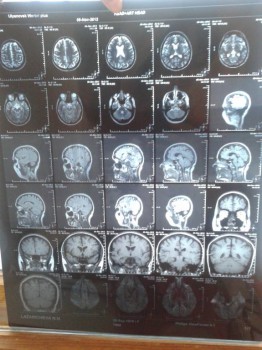

Здравствуйте. Мне 37 лет. С детства страдала мигренью. В 2012 году был приступ ТИА головного мозга. Диагноз МРТ: умеренная наружная и бивентрикулярная гидроцефалия. Признаки ДЭ. Малый диаметр ЛПА. Субокклюзия ЛПА выше места отхождения ЛЗНМА. Периодически страдаю головокружениями, звон в ушах постоянный, бывает тошнота, головные боли, блики в глазах. Есть шейный остеохондроз. Сотрясений и ушибов не было. Что означает мой диагноз, возможно ли излечение и его методы? Спасибо.